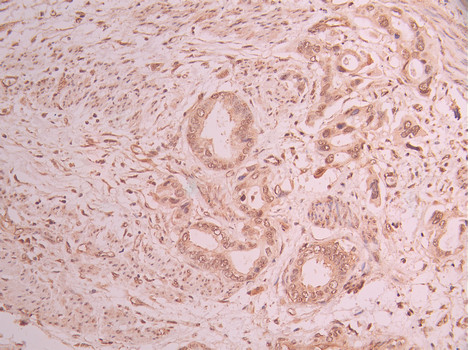

IHC image of CSB-RA948135A0HU diluted at 1:100 and staining in paraffin-embedded human cervical cancer performed on a Leica BondTM system. After dewaxing and hydration, antigen retrieval was mediated by high pressure in a citrate buffer (pH 6.0). Section was blocked with 10% normal goat serum 30min at RT. Then primary antibody (1% BSA) was incubated at 4°C overnight. The primary is detected by a Goat anti-rabbit polymer IgG labeled by HRP and visualized using 0.05% DAB.